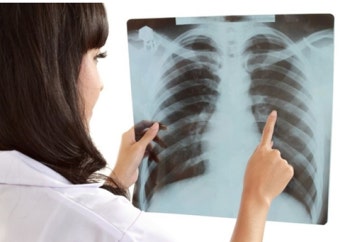

전문의의 X-ray 또는 CT 진단을 통해 결정됩니다.